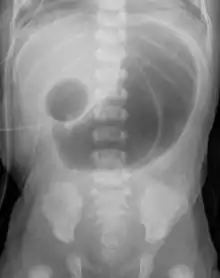

| Radiograph with double bubble sign indicating duodenal atresia | |

If not diagnosed in utero, infants with intestinal atresia are typically diagnosed at day 1 or day 2 after presenting with eating problems, vomiting, and/or failure to have a bowel movement.[3] Diagnosis can be confirmed with an X-ray, and typically followed with an upper gastrointestinal series, lower gastrointestinal series, and ultrasound.[5][3]